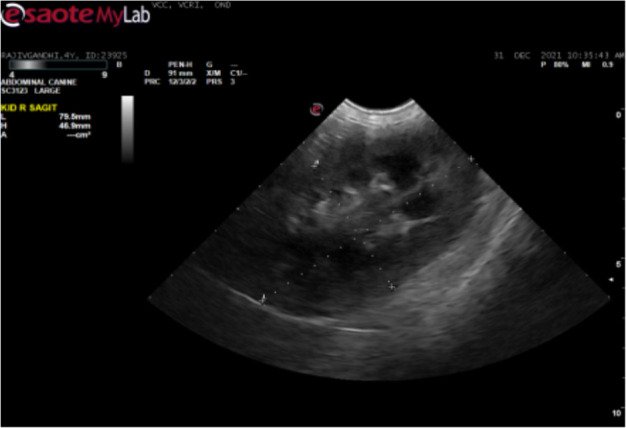

锥虫是红细胞外的血鞭毛原虫,寄生于包括狗在内的家养和野生动物体内。一只雄性罗威纳犬因厌食、眼睛浑浊和呕吐一周而就诊。对该犬进行了身体和临床检查。采集了血液并进行了血液学和生化分析。进行了胸腔超声心动图和腹腔超声波检查。通过 PCR 对寄生虫进行了分子确认,并对 DNA 进行了测序,以确定菌株变异。经临床检查,该犬消瘦,伴有高烧、单侧角膜混浊、贫血、淋巴结肿大和腹部膨胀。胸腔超声心动图显示心室肥大和心肌病。腹腔超声波检查显示脾脏肿大和肾脏肿大。血液学检查结果显示血红蛋白和红细胞计数下降,生化检查结果显示尿素氮和肌酐升高、低血糖和低白蛋白血症。湿片和血涂片检查分别显示锥虫运动活跃和锥虫大量感染。通过扩增 evansi 锥虫的 227 bp 部分 VSG 基因进行了分子鉴定,随后进行了测序和系统发育分析。感染犬在接受支持疗法的同时,肌肉注射醋酸地米那嗪(3.5 毫克/千克体重)。该研究描述了犬锥虫病的发生和诊断。早期诊断和及时治疗是保护伴侣动物的最可靠方法。这是印度泰米尔纳德邦考弗里三角洲地区首次报告犬锥虫病。

Trypanosomes are the extraerythrocytic haemoflagellate protozoan parasites of domestic and wild animals including dogs. A male Rottweiler dog was presented with the history of anorexia, cloudy eyes and vomiting for a week. The dog was examined both physically and clinically. Blood was collected and subjected to haematological and biochemical analysis. Echocardiography of the thoracic cavity and ultrasonography of the abdominal cavity were performed. Molecular confirmation of parasite was carried out by PCR and DNA was sequenced to identify strain variations. Upon clinical examination, the dog revealed emaciation with high fever, unilateral corneal opacity, anemia, enlarged lymph nodes and distended abdomen. Echocardiography of the thoracic cavity showed ventricular hypertrophy and cardiomyopathy. Ultrasonography of the abdominal cavity showed splenomegaly and renomegaly. Haematological findings revealed decreased haemoglobin and erythrocyte count and biochemical findings revealed increased BUN and creatinine, hypoglycemia and hypoalbuminemia. Wet film and blood smear examination revealed actively motile trypanosomes and massive infection of trypanosomes, respectively. Molecular confirmation of species was carried out by amplification of 227 bp partial VSG gene of Trypanososma evansi, subsequently sequenced and phylogenitically analysed. The infected dog was treated intramuscularly with diminazene aceturate @ 3.5 mg/kg b.wt along with the supportive therapy. The study described the occurrence and diagnosis of trypanosomosis in dog. Early diagnosis and timely treatment is the most reliable way to safeguard the companion animals. It is the first report on trypanosomosis in dog from Cauvery delta region of Tamil Nadu, India.